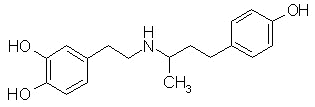

Dobutamine (Dobutrex)

Dobutamine (Dobutrex)is a racemate that binds to

and activates

-1 and

-2 adrenoceptor subtypes.

The (-) enantiomer stimulates

1 and a

2 receptors, but this effect in humans appear

negated by binding of the inactive (+) enantiomer.

Therefore the positive inotropic action mediated by beta receptor activation predominates.

Dobutamine (Dobutrex) does not activate dopamine receptors and therefore does not increase renal blood flow.Because of its vasodilator properties, dobutamine's positive inotropism is accompanied by a decrease in afterload. For this reason dobutamine may be favored over dopamine for most advanced heart failure patients who have not improved with digoxin (Lanoxin, Lanoxicaps) , diuretics, and vasodilator therapy.